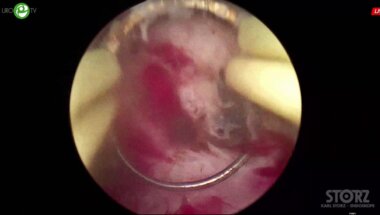

Зубков И.В. - П-ТУЭП (плазменная)

14 дек 2020